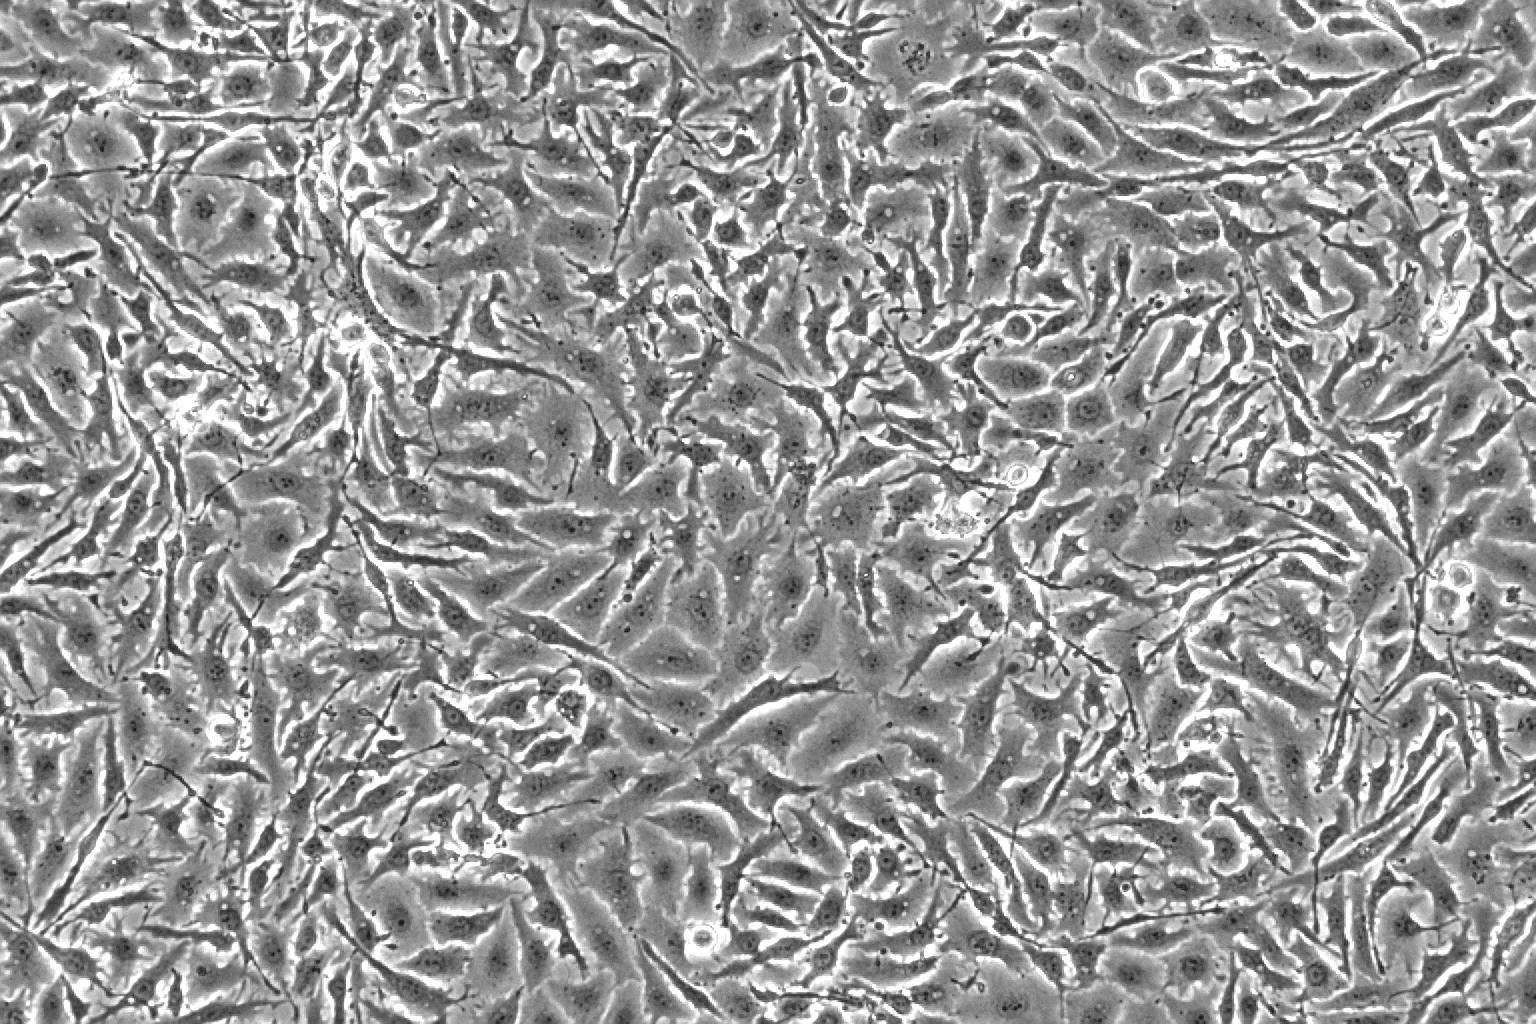

细胞形态上皮细胞样

生长特性贴壁生长

NCI-H1650细胞是于1987年从一名27岁白人男性(10年烟龄)支气管肺泡癌患者的胸腔积液中分离得到的